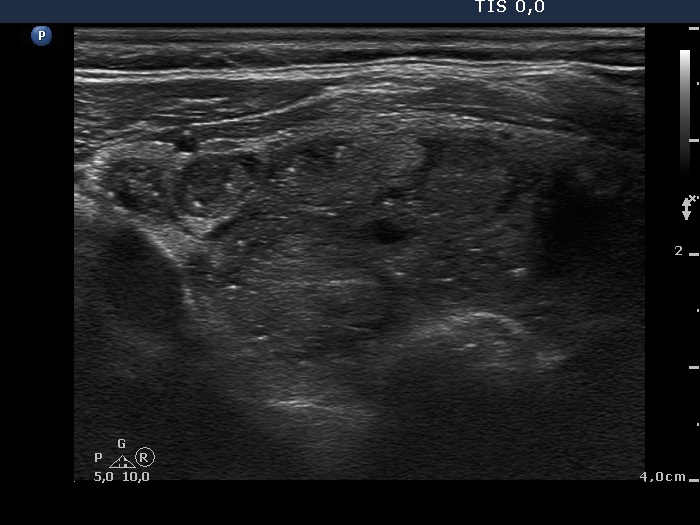

Benign hyperplastic nodule (histological diagnosis) - case cons037 |

Upper part of the right lobe |

|

The bright hyperechogenic granules (arrows) seem to be at first sight punctate echogenic foci. However, the presence of a few hyperechogenic lines (arrowheads) challenges this view: these figures might be presentations of a connective tissue.

Lower part of the right lobe

This nodule has multiple coarse calcifications and proliferation of a connective tissue (arrowheads and arrows).